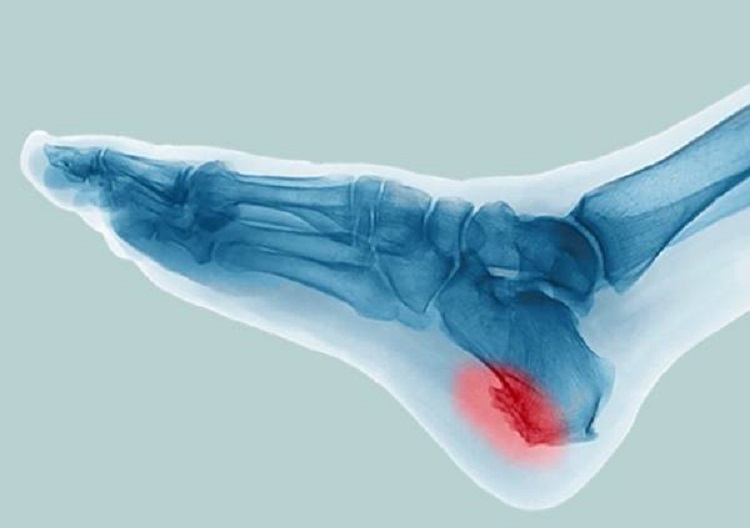

فرارو- خار پاشنه (استئوفیت یا زائده استخوانی) زائده استخوانی کوچک یا مجموعه زائده‌های استخوانی است که پشت پاشنه یا زیر آن ایجاد می‌شود. خار پاشنه پا می‌تواند همراه با درد یا بدون درد باشد. بیماران غالباً خار پاشنه پا را با عارضه دیگری به نام التهاب رباط کف پا (التهاب پلانتار فاسیا) اشتباه می‌گیرند که در آن، نوار بافتی کشیده شده از برجستگی کف پا تا پاشنه، یعنی همان پلانتار فاسیای ایجاد کننده قوس کف پا، ملتهب و منجر به درد کف پا و پاشنه پا می‌شود. بسیاری از افراد هیچ‌گاه متوجه وجود خار پاشنه نمی‌شوند. خار پاشنه احتمالاً هنگامی شکل می‌گیرد که بدن با ایجاد استخوان اضافی در محل ضربه و صدمه دیدن در صدد ترمیم آسیب‌های مکرر برمی‌آید. اگر با عارضه و التهابی در پاشنه پای خود مواجه هستید و نمی‌دانید علت آن چیست و چگونه باید آن را درمان کنید، این مطلب می‌تواند به شما اطلاعات جامعی در این زمینه دهد.

خار پاشنه پا چیست؟

خار پاشنه در واقع یک زائده‌ی استخوانی است که در زیر استخوان پاشنه پا شکل می‌گیرد. در گذشته تصور می‌شد که خار کف پاشنه پا به به دلیل بخشی از تنش (کشش طولی) بافت نرم مانند پلانتار فاسیا بر روی استخوان ایجاد می‌شود، اما تحقیقات اخیر نشان می‌دهد که خار کف پاشنه پا بیشتر به دلیل واکنش انطباقی به فشار عمودی (محوری) در استخوان پاشنه پا شکل می‌گیرد. خار پشت پاشنه پا که باعث تغییر شکل غیر طبیعی استخوان کالکانئال می‌شود، می‌تواند به دلیل واکنش به سفت شدن غیر عادی تاندون آشیل ایجاد شود که موجب التهاب مزمن تاندون و شکل‌گیری استخوان واکنشی (راکتیو) در آن محل شود.

اگر فردی این علائم را داشته باشد، پزشک برای تشخیص مشکل او از اشعه‌ی ایکس استفاده می‌کند. مشاهده‌ی برآمدگی با استفاده از اشعه‌ی ایکس، تنها راه اطمینان یافتن از وجود مشکل خار پاشنه در فرد است. البته تمام علائم بالا در همه‌ی افرادی که دچار خار پاشنه هستند، مشاهده نمی‌شود. بعضی از افراد مبتلا به خار پاشنه هیچ علامتی ندارند. این افراد تنها زمانی متوجه خار پاشنه‌ی خود می‌شوند که پای آن‌ها به‌دلیل مشکل دیگری توسط اشعه‌ی ایکس بررسی شود.